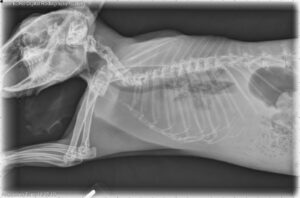

Radiology is a frequently underutilized diagnostic tool in the medical and surgical care of rabbits.

As companion rabbits live longer, the diagnosis of cardiac disease has become more common, influenced by factors such as age, genetics, concurrent diseases, and diet, affecting various parts of the heart including muscles, valves, and electrical conduction.